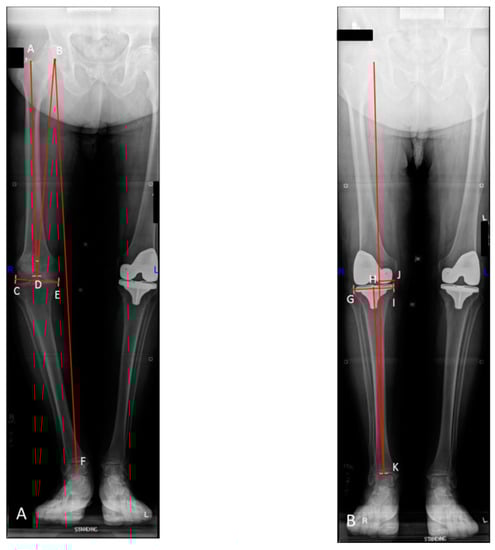

2.3. Radiographic Analysis